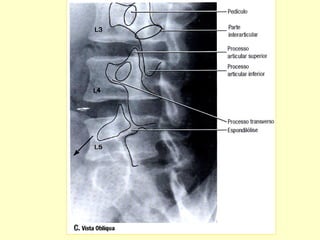

Incidências Básicas

Radiografias em A P e Perfil .

Para verificações dos forames intervertebrais

como também para avaliação dos arcos

posteriores , acrescentar incidências obliquas.

C – Vista Lateral